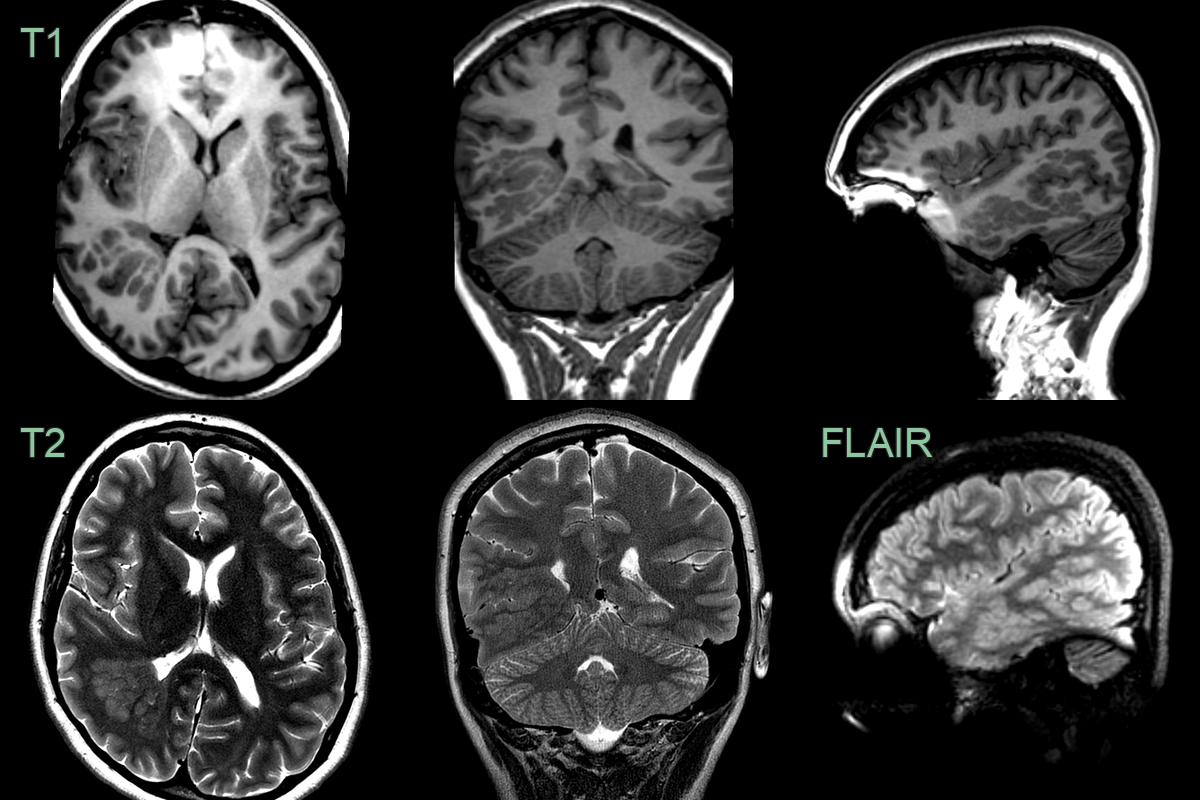

• Extensive periventricular grey matter heterotopia in a patient with epilepsy.